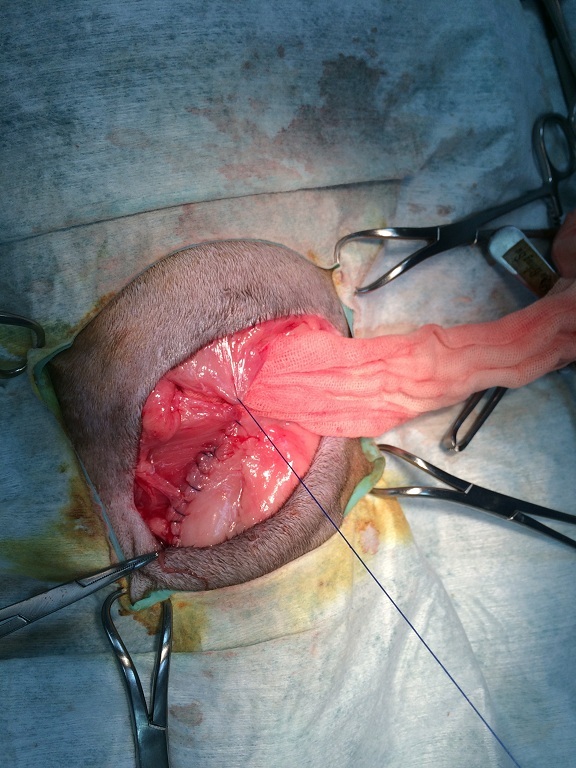

故醫生排定在1/27做修補手術,

乖妹在疝氣修補手術完成之後,

恢復情況良好穩定,

雖然乖妹為了手術需要開的引流管有點出血的情況,

不過在照護員每天擦優碘之後傷口就痊癒了。

手術的縫線在兩週後2/11就回醫院拆掉縫線,

這才讓照護員們都鬆了一口氣。